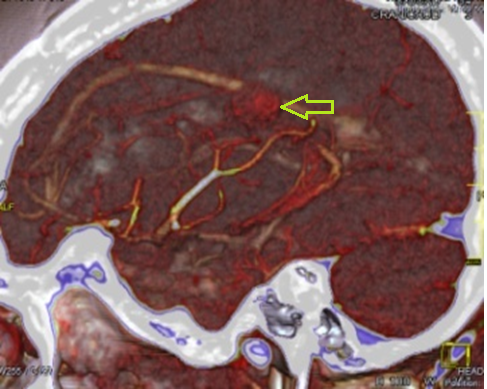

A non-contrast and subsequent intravenous contrast-enhanced axial computed tomography scan of the head was carried out. It revealed a hyperdense, rounded lesion with a whorled appearance and a density of 54 HU, located in the left parietal lobe (Figure 1 a, b, c). A CT angiography of the head showed a hyperdense (54 HU), rounded, whorled-appearing lesion located in the left parietal lobe within the territory of the middle cerebral artery, with drainage into the inferior sagittal sinus (Figure 2).

Fig. 2 - CT angiography of the head, sagittal sequence, showing the arteriovenous nidus as a rounded image indicated by a yellow arrow.